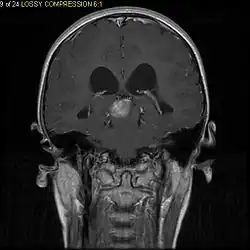

Pilocytic astrocytoma (and its variant pilomyxoid astrocytoma) is a brain tumor that occurs most commonly in children and young adults (in the first 20 years of life). They usually arise in the cerebellum, near the brainstem, in the hypothalamic region, or the optic chiasm, but they may occur in any area where astrocytes are present, including the cerebral hemispheres and the spinal cord. These tumors are usually slow growing and benign, corresponding to WHO malignancy grade 1.[1]

Usually – depending on the interview of the patient and after a clinical exam which includes a neurological exam and an ophthalmological exam – a CT scan and/or an MRI scan will be performed to confirm the presence of a tumor. They are usually easily distinguishable from normal brain structures using these imaging techniques. A special dye may be injected into a vein before these scans to provide contrast and make tumors easier to identify. Pilocytic astrocytomas are typically clearly visible on such scans, but it is often difficult to say based on imaging alone what type of tumor is present.